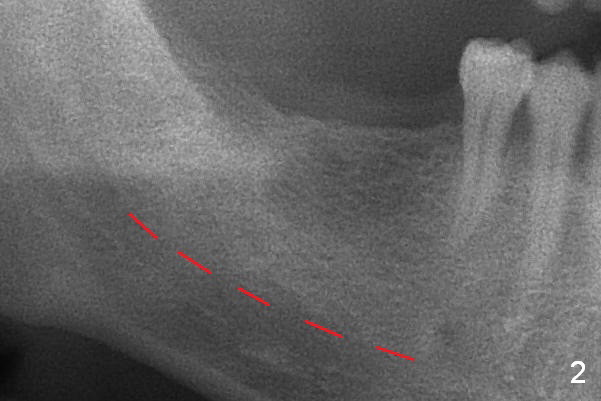

A 54-year-old man has multiple restoration (Fig.1). The curve of Spree on the right side is abnormal (arrow with #2 supraocclusal; #3 and 4 infraocclusal).  Bone density at the sites of #30 and 31 appears to be low.  Prepare bone expansion.

The bone height is good (Fig.2 (red dashed line: the superior border of the Inferior Alveolar Canal)).  Implants at #30 and 31 are expected 5x12 or 14 and 5x10 or 12 mm, respectively.  The abutments are 6.8x4(2) and 6.8x4(1) mm.